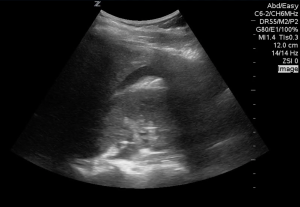

Here is the initial RUQ view of a patient who sustained blunt abdominal trauma.

There is a hint of a black strip, granted we can’t see the entire sweep but if this was all there was I would hesitate to commit to surgical intervention.

here is the same patient 10 mintues later…

Now it’s unmistakable, performing serial fasts has shown to improve the overall sensitivity, especially if using only the RUQ view. With pelvic binders and foley catheters a definitive pelvic view is often difficult, but remember space in the pelvis is limited, it will declare itself if it is present.